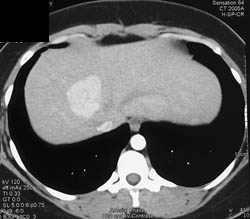

Focal Nodular Hyperplasia (FNH)